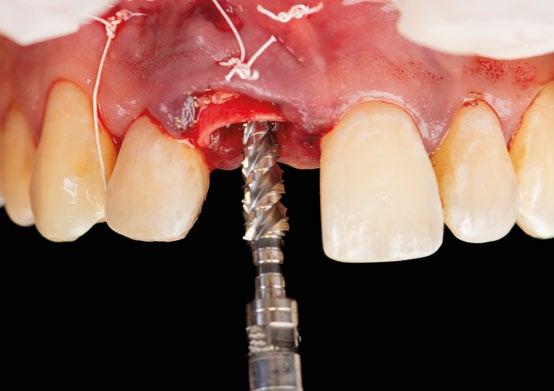

8.- Realizamos osteotomía mediante férula quirúrgica utilizando fresa piloto. (Figuras 22 a 24)

9.- Seguimos preparando el lecho utilizando fresado biológico con la OsseoShaperTM. (Figura 25)

10.- Colocamos implante Nobel Biocare N1TM TiUltra de 3,5x13. (Figura 26)